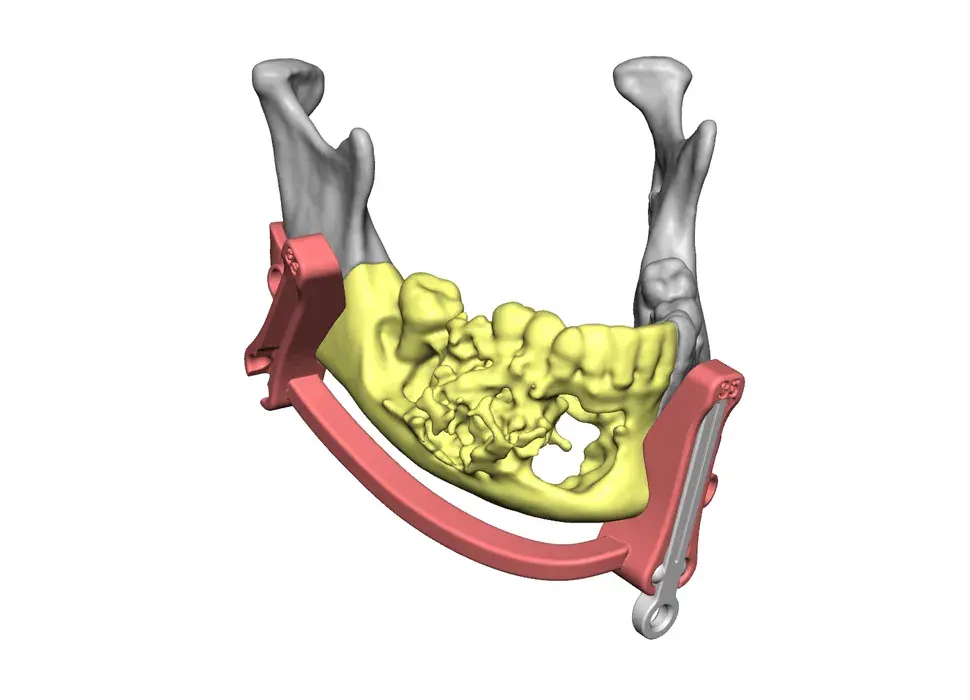

3D Systems' VSP® surgical planning solutions for craniomaxillofacial (CMF) applications received FDA clearance as a service-based approach to personalized surgery over 10 years ago.

3D Systems and Stryker Corporation have partnered to provide surgeons with best-in-class products and services for craniomaxillofacial surgeries. As a leader in personalized healthcare solutions, 3D Systems has planned and delivered devices for more than 140,000 patient-specific cases. The Stryker Craniomaxillofacial business specializes in providing patient-specific options and innovative solutions that help drive efficiencies in surgical suites. The combination of Stryker’s specialized team and advanced implants with 3D Systems' cutting-edge 3D printing technologies and expert consulting services positions both companies to provide a superior level of service to healthcare professionals who use these revolutionary solutions.